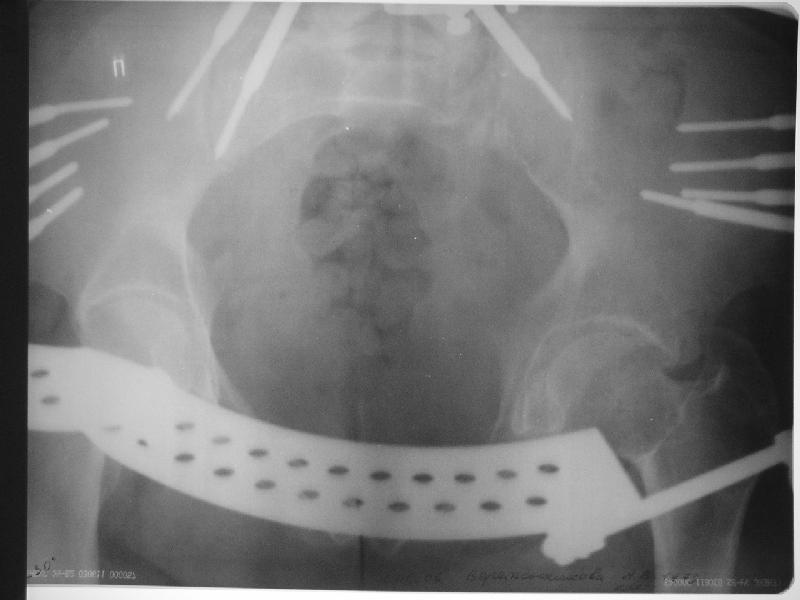

Прооперировали молодую девушку 32 лет спустя 9 мес после травмы. Имелся стойкий болевой синдром, неопороспособность левой н/конечности, моторные и сенсорные нарушения в левой голени и стопе, патологическая подвижность левой половины таза. Первым этапом закрыто в аппарате исправили деформацию ( в течении 2,5 нед). Вторым закрытое введение илиосакральных винтов в крестец (канюллированные 7,2 мм Chm) + туннелизация зоны псевдоартроза спицама Киршнера, реконструкция передних отделов таза, накостный остеосинтез . Аппарат частично демонтирпован, оставлена "передняя рама" После устранения деформации отмечен регресс неврологической симптоматики, уменьшение болевого синдрома. Интересующие вопросы: 1. Прогноз для сращения псевдоартроза крестца. 2. сроки нагрузки весом левой половины таза. Буду очень признателен за ваши мнения по этому поводу.A female 32 y.o. admitted to our unit 9 months after initial injury with pain, inability to bear weight at the left lower limb, sensor and motor disturbances in the left foot and tibia, with mobility of the left hemipelvis.At first closed reduction was performed by an external fixator within 2,5 weeks. After correction her pain decreased and some neurological progress was achieved. Now two iliosacral screws 7,2 mm were inserted, and anterior lesion was fixed by a plate. External fixator was partially unmounted, only anterior frame left in place.Images attached.How would you evaluate chances of healing of the sacrum with the current position?When would you allow weight-bearing of the left leg?THX in advance.

Примерно такой фиксатор наложил вчера ночью, но патология была экстренная травма: больному 53 года, поступил после мотоциклетной травмы, черепно-мозговой, абдоминальной, челюстно лицевой с потерей одного глаза, сосудистой и из скелета перелом крестца слева с диастазом симфиза и множественные переломы ребер.

Здесь соблюдался алгоритм больному с внутритазовым кроветечением после нестабильного перелома таза.

Одновременно с хирургами, которые занялись ксплоративной лапаротомией, мы приступили к фиксации временным аппаратом для уменьшения диастаза симфиза. После установки аппарата удалось стабилизировать давление, потом наше место занял сосудистый хирург, который нашел кровоточащую левую артерию epigastrica. Кровоточаший сосуд затромбизировал эндоваскулярно введением 4 coil placement.